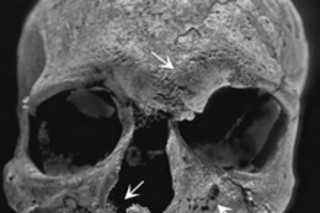

A close examination of the skull showed eroded pits typical of advanced leprosy, as well as tooth loss and root exposure. Experts on leprosy have debated whether the disease was disseminated when humans originally left Africa and began to spread out over the globe, or whether it began to circulate and spread from India in a more recent age. The new study, published in the journal PLoS ONE, supports the idea that the disease didn't really catch hold until humans began clustering together in cities, and engaging in long-distance trade.